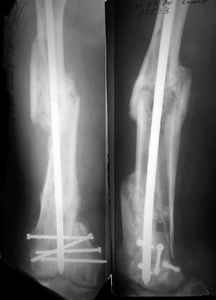

1. Percutaneous nailing is truly minimally invasive technique, but, unfortunately, nails are not reliable in many hands.

Attached are few examples from our Hospital:

A. Difficult reductions, even in retrograde nailing (my preference, easier control of "small" distal fragment) and it is much, much harder to do it anterograde (Alex, do you have one good case in your collection of anterograde nailing in very distal fractures - as you have suggested that I

should have done it in my previously posted case?

Malpositioning is much too common (recurvatum, varus - valgus).

B. Fixation loosening: distal cutting of the nail, non-unions do happen (cases attached).

Locking Plating has more distal screws than any nail, fixed angles and provides much better fixation, especially in osteoporotic bone.

KEMMD> B. Fixation loosening: distal cutting of the nail, non-unions do happen

KEMMD> (cases attached).

The nail can be unlocked in the proximal fragment to prevent it.